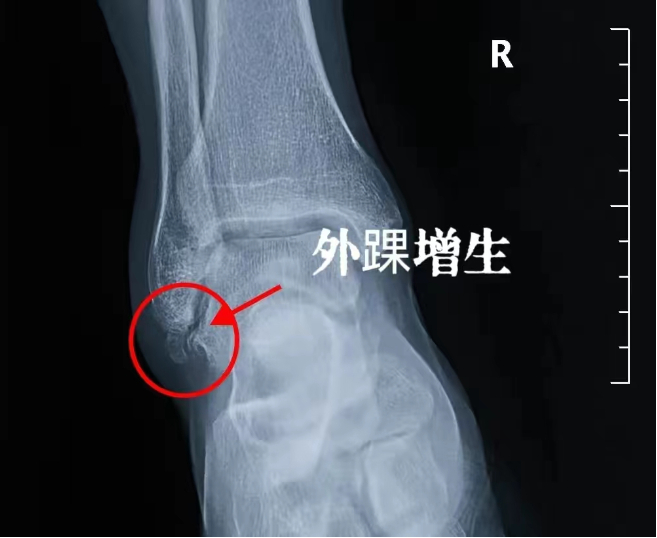

经过查体我们进行了x线检查,他的外踝有明确的骨质增生,关节间隙发生了狭窄。在侧位上谢医生做了红色的圆圈标记,这是一个非常严重的增生,仿佛在胫骨的远端长出了一个菜花,那这个增生的部位就会导致患者出现蹲起时踝关节的疼痛,它不可能是几年的时间形成的,需要的时间很漫长。

我们仔细看踝关节的后方,感觉还有一个瘤巢,有一些非常细小的星星、点点的高亮的影像,被包膜包裹住了,很有可能是滑膜软骨瘤形成。